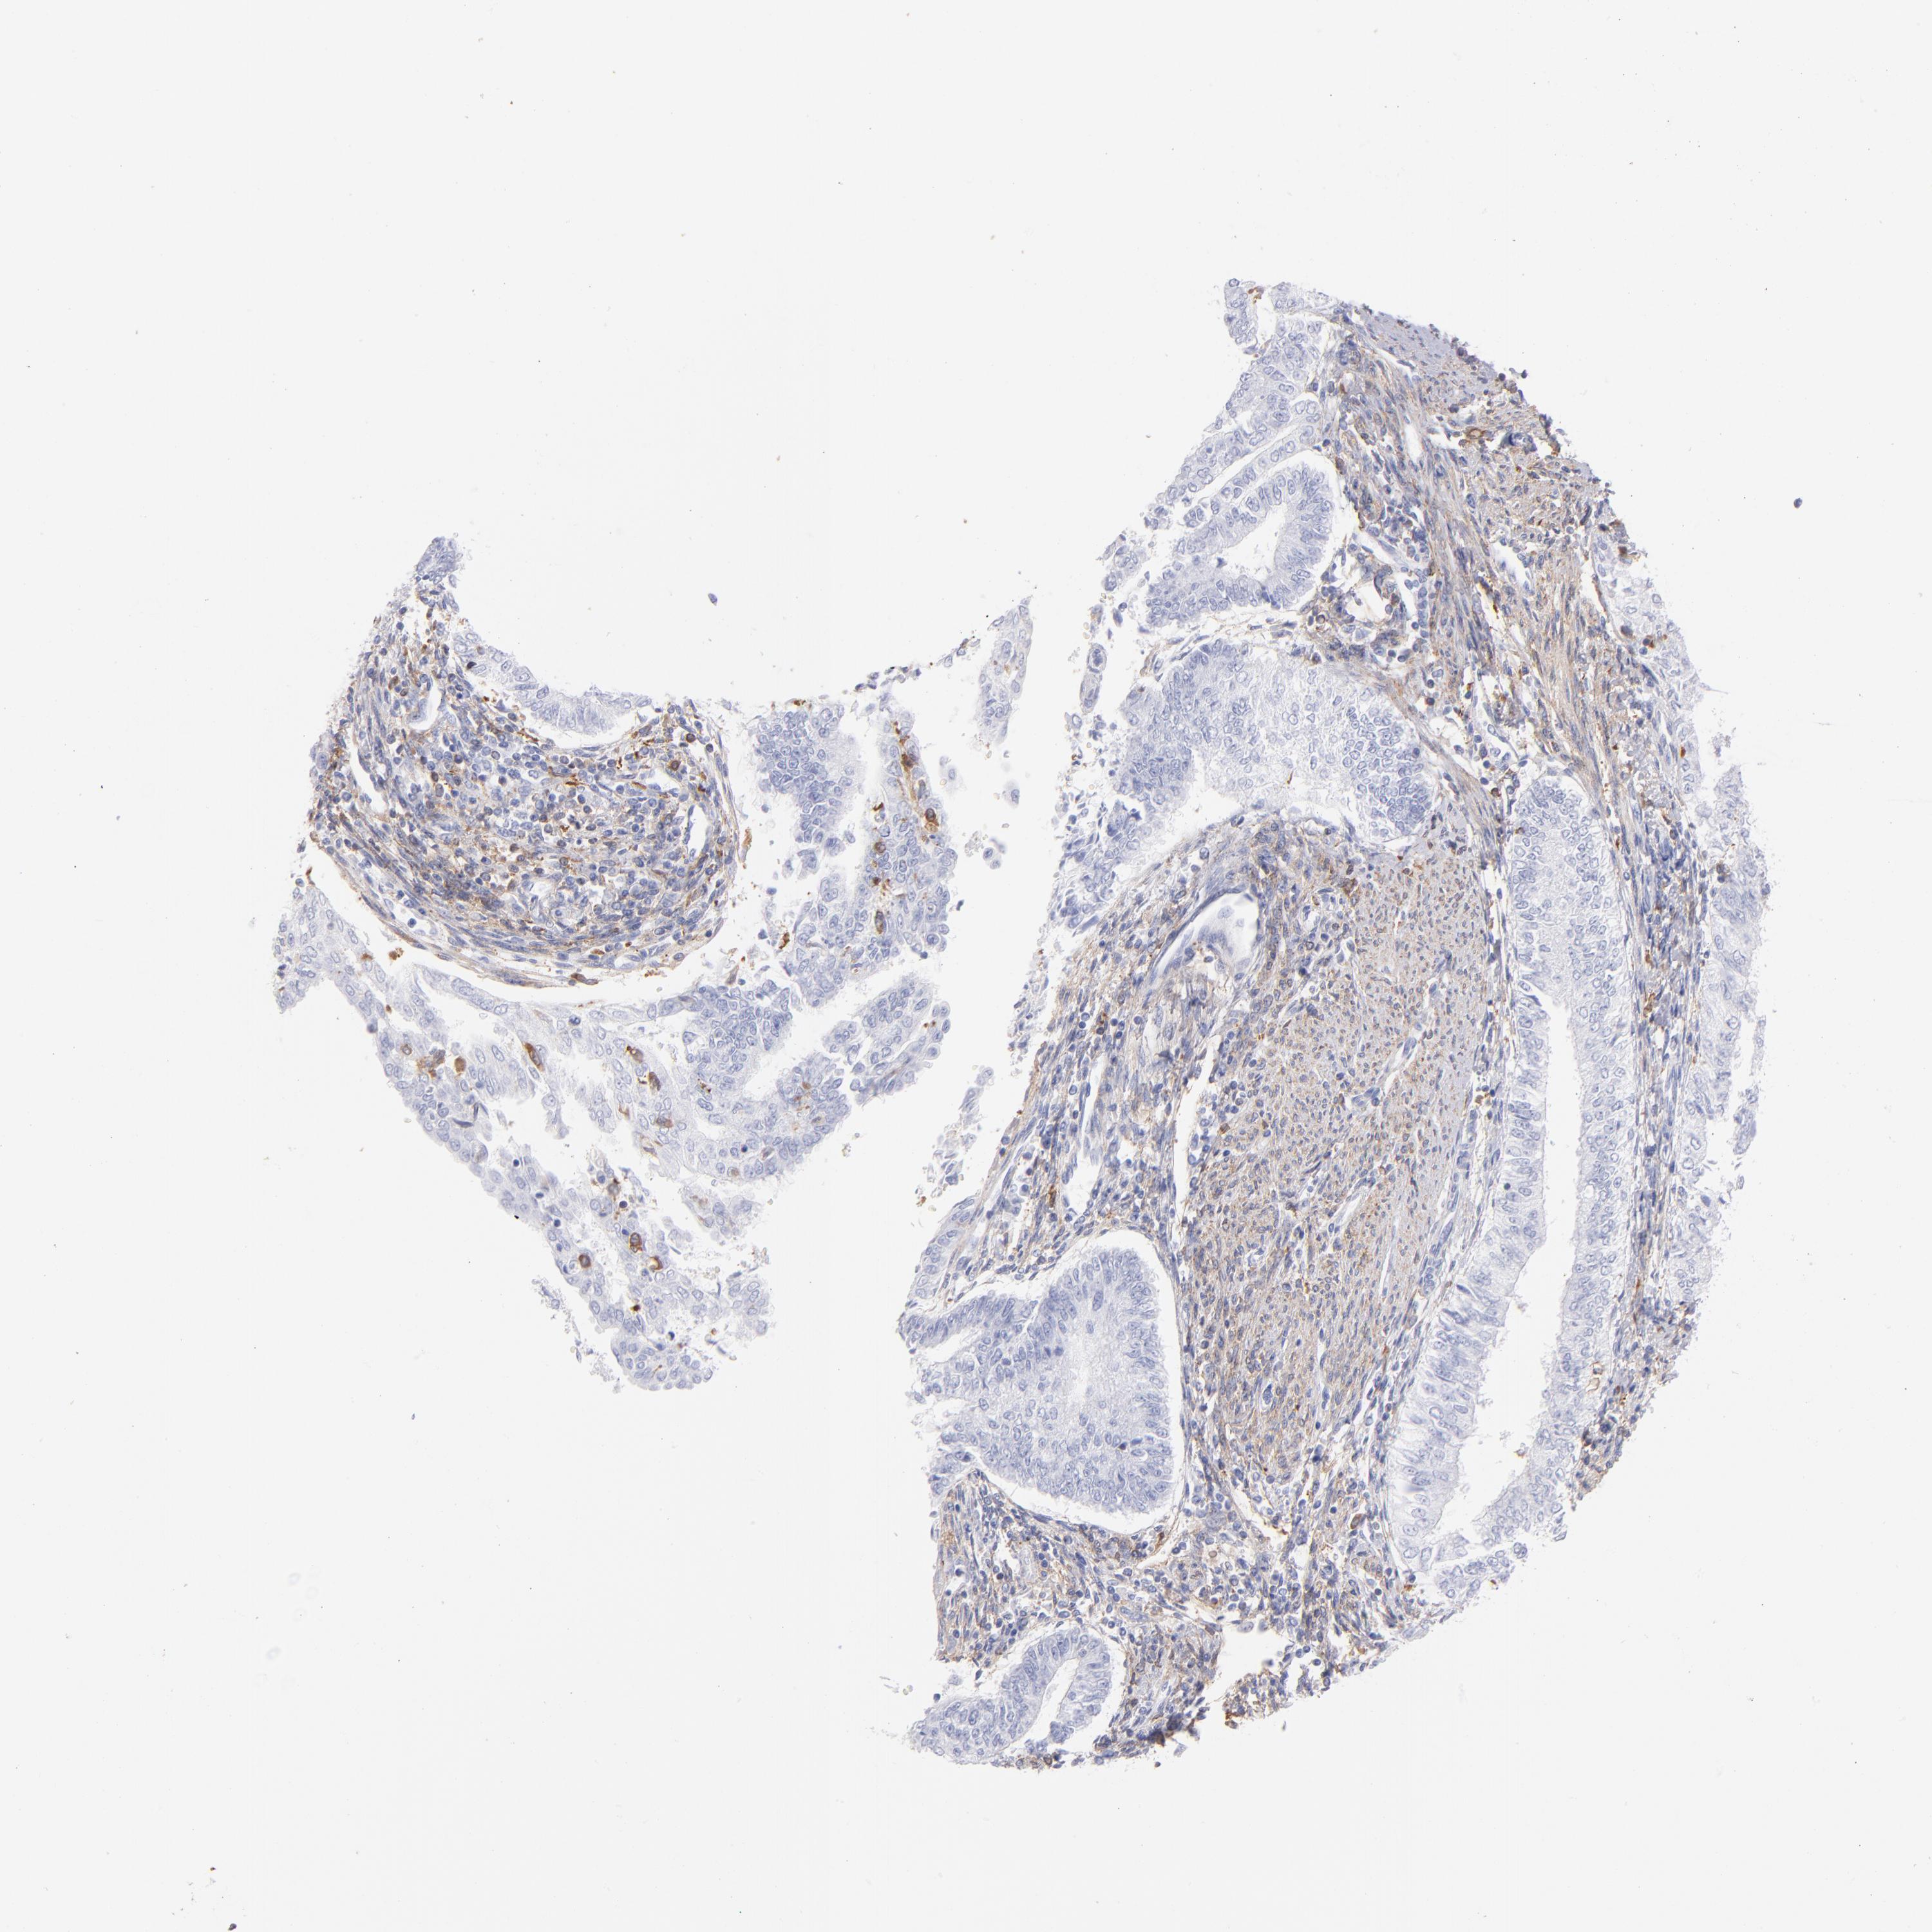

ENDOMETRIAL CANCER - Protein expressioni

A mouse-over function shows sample information and annotation data. Click on an image to view it in a full screen mode. Samples can be filtered based on level of antibody staining by selecting one or several of the following categories: high, medium, low and not detected. The assay and annotation is described here.

Note that samples used for immunohistochemistry by the Human Protein Atlas do not correspond to samples in the TCGA dataset.

Antibody stainingi

Antibody staining in the annotated cell types in the current human tissue is reported as not detected, low, medium, or high, based on conventional immunohistochemistry profiling in selected tissues. This score is based on the combination of the staining intensity and fraction of stained cells.

Each image is clickable and will lead to virtual microscopy that enables deeper exploration of all samples and also displays staining intensity scores, fraction scores and subcellular localization as well as patient and tissue information for each sample.

Antibody HPA006563

Antibody HPA006564

Antibody CAB003844

Antibody CAB016290

Staining

High

Medium

Low

Not detected

Intensity

Strong

Moderate

Weak

Negative

Quantity

>75%

75%-25%

<25%

None

Location

Nuclear

Cytoplasmic/membranous

Cytoplasmic/membranous,nuclear